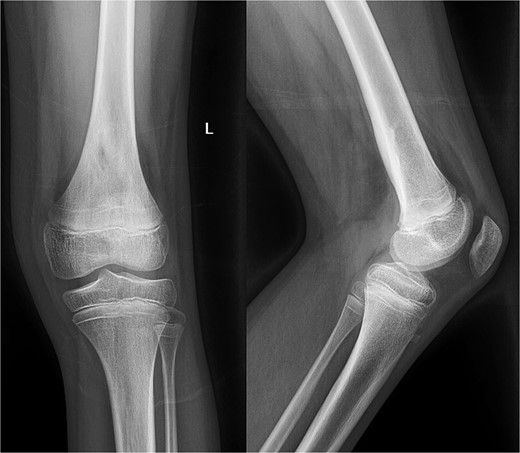

Despite initial improvement, the patient’s CRP stabilized at 5.5 μg/ml 6 days post-operatively. Consequently, a repeat I&D with antibiotic bead placement was performed on postoperative Day 7. The patient’s condition improved, with undetectable CRP levels at discharge 14 days after initial hospitalization. Four weeks post-discharge, a repeat venous ultrasound of the affect extremity was performed, demonstrating resolution of the DVT (Fig. 2). In total, the patient received 18 weeks of outpatient oral antibiotic therapy and 9 weeks of anticoagulation therapy. Six months post-hospitalization, the patient was asymptomatic and cleared to return to full activity. After 1-year post-discharge, final radiographs demonstrated no osseous abnormalities, the patient remained asymptomatic, and was released from clinic (Figs 3 and 4).

Radiography obtained 1-year postoperatively, demonstrating no acute osseous changes.